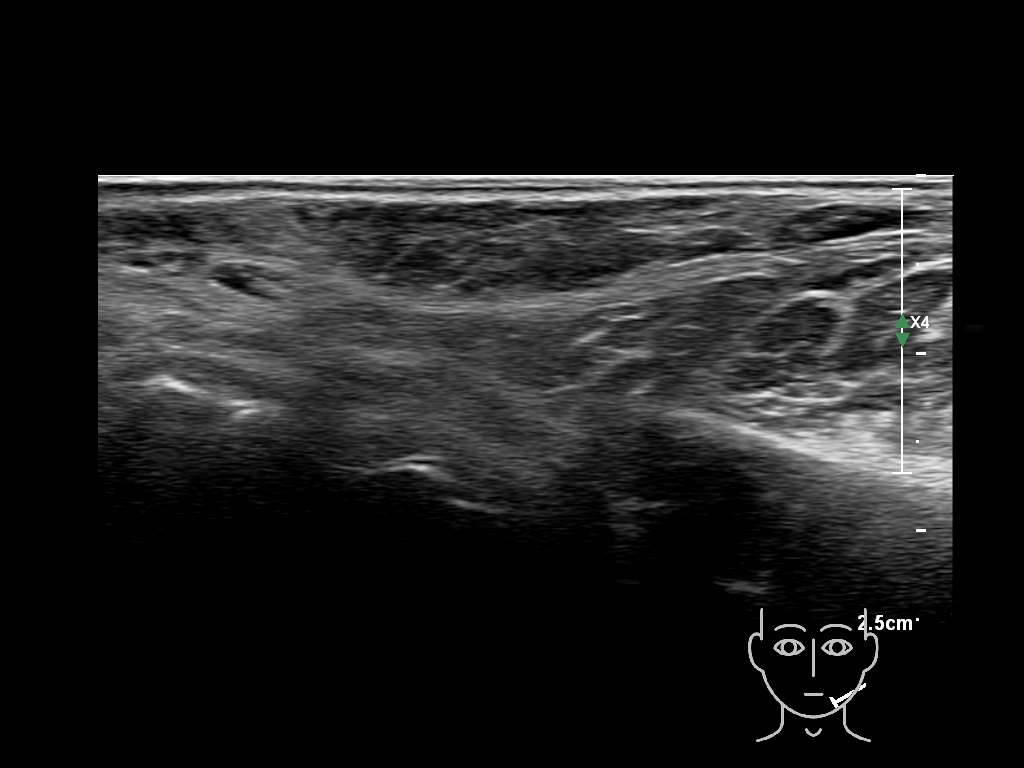

Draw in the second image below where the fillers are located. To check if your answer is correct, swipe the first image to the right.

Filler library

HAca 2a

HAca 3a

HAca 3a

HAca 4a